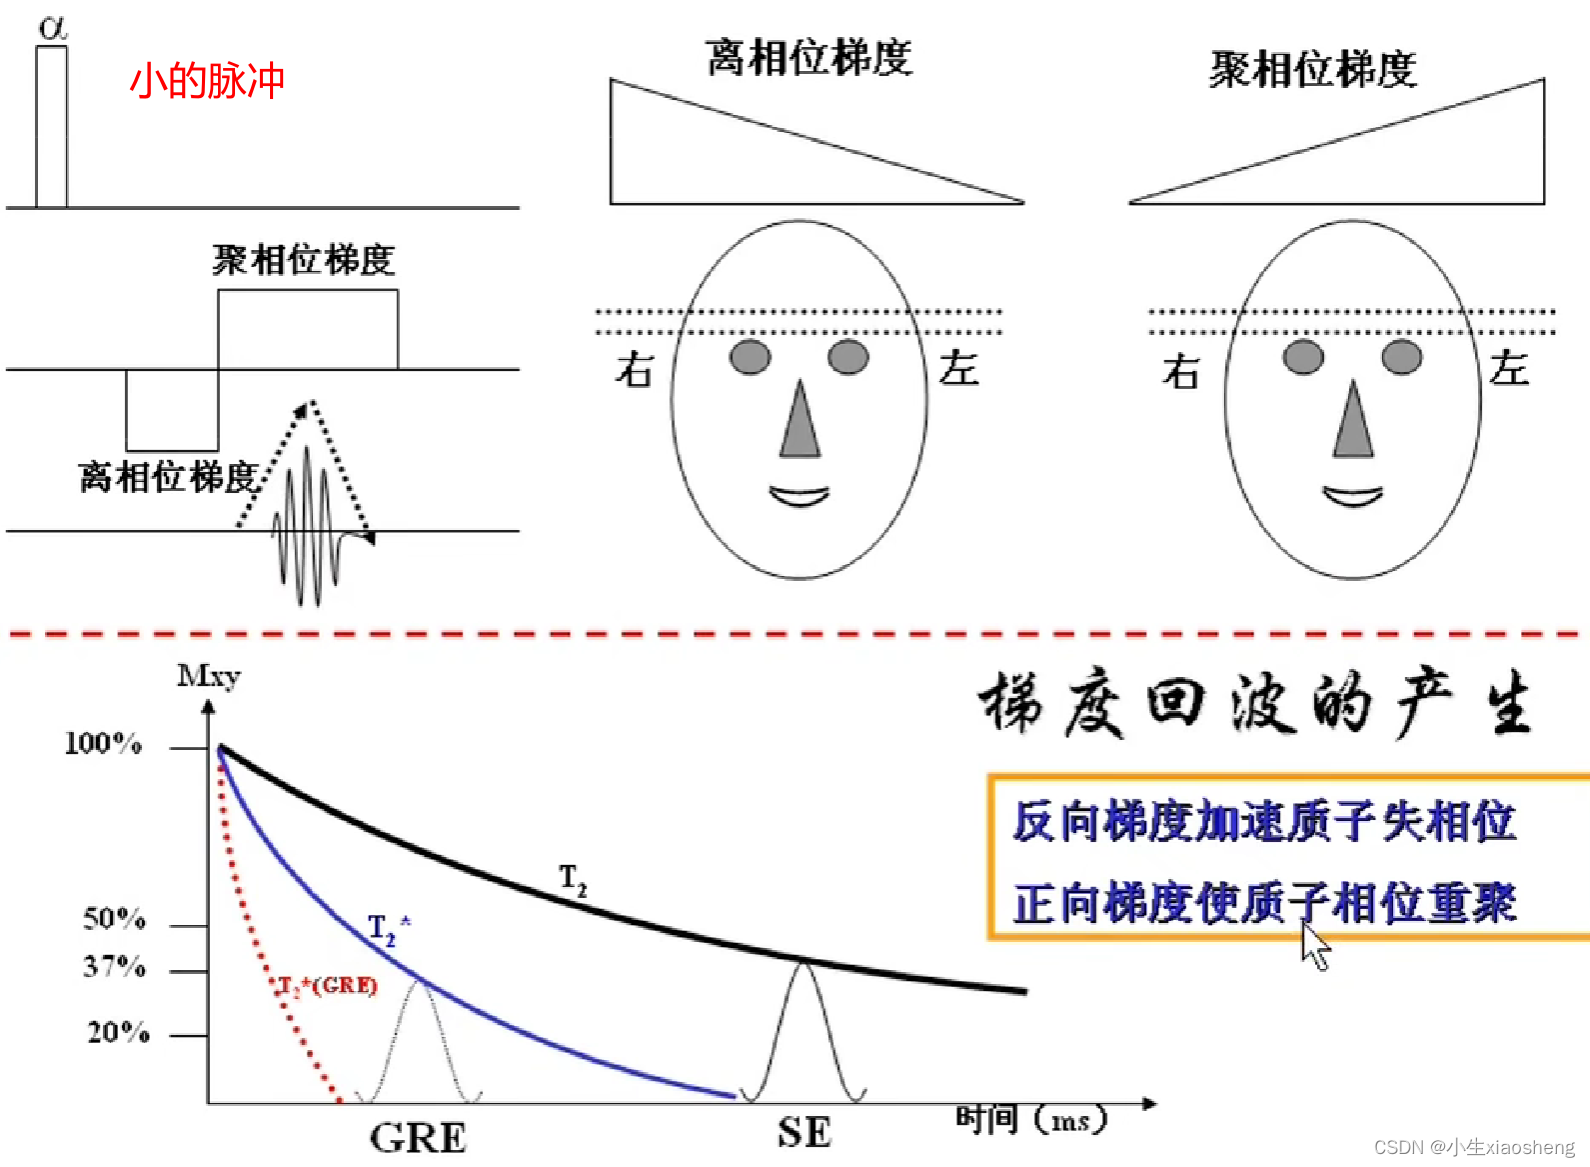

五、梯度回波类序列

GRE就是梯度回波